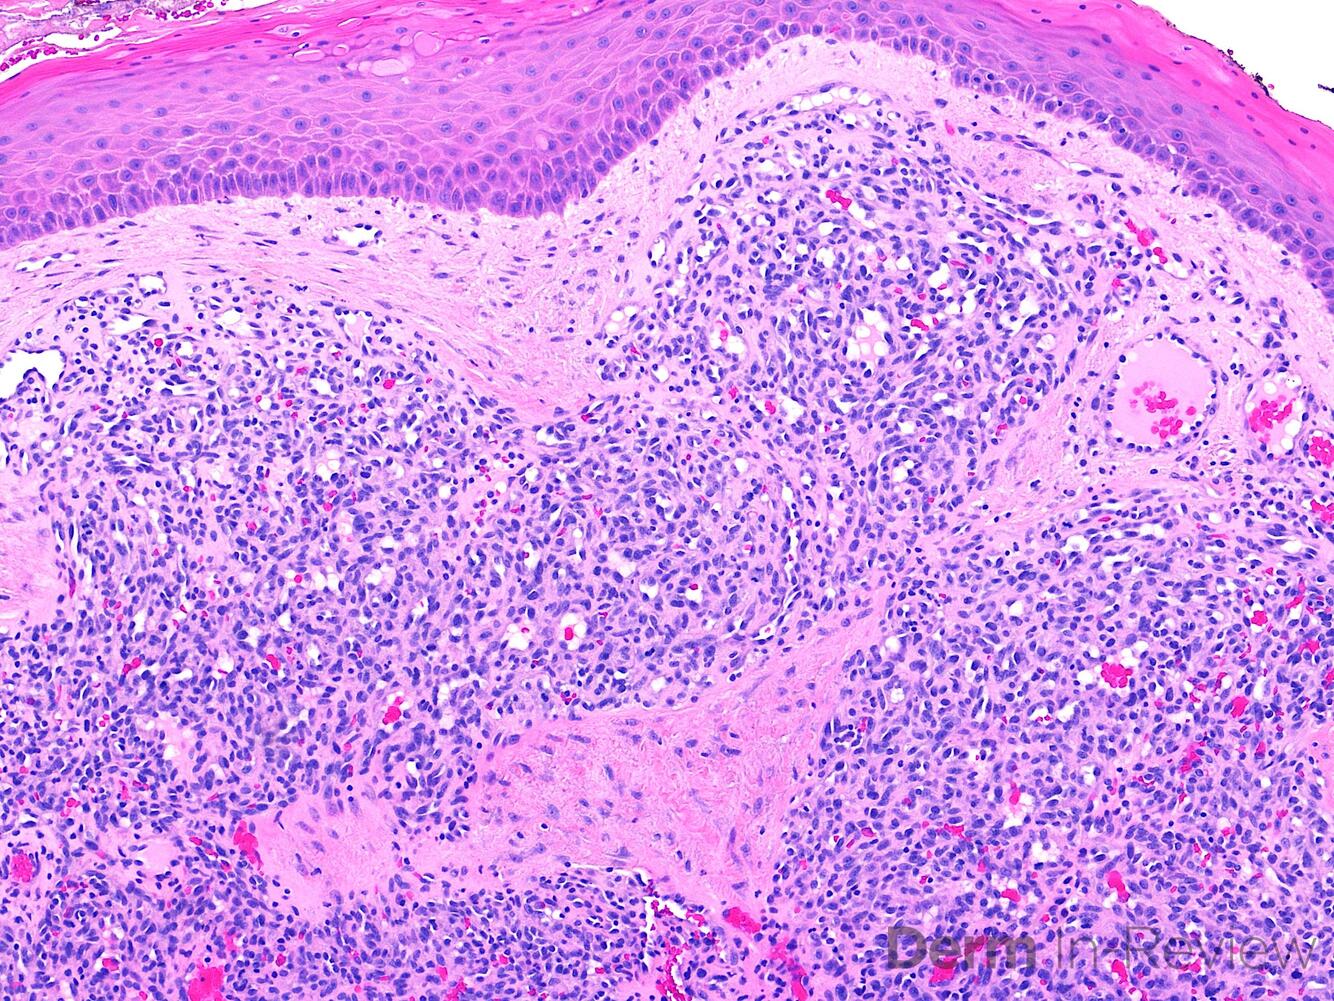

33

33. The pathology seen here is taken from a 68-year-old male with a diffuse skin eruption, with few blisters and crusting on the oral mucosa. Which of the followin is the most likely diagnosis? A. Lupus erythematosus (chronic or discoid) B. Pemphigus vulgaris C. Tumid lupus D. Porphyria cutanea tarda E. Bullous pemphigoid

Correct choice:B. Pemphigus vulgaris Explanation: The suprabasal acantholysis that extends down adnexal structures is most consistent with pemphigus vulgaris. Chronic discoid lupus and tumid lupus will have superficial and deep perivascular lymphoid infiltrates and dermal mucin.PCT will have a cell-poor subepidermal vesicle and thickening of superficial dermal blood vessels. Bullous pemphigoid will have a cell-rich subepidermal vesicle with eosinophils.